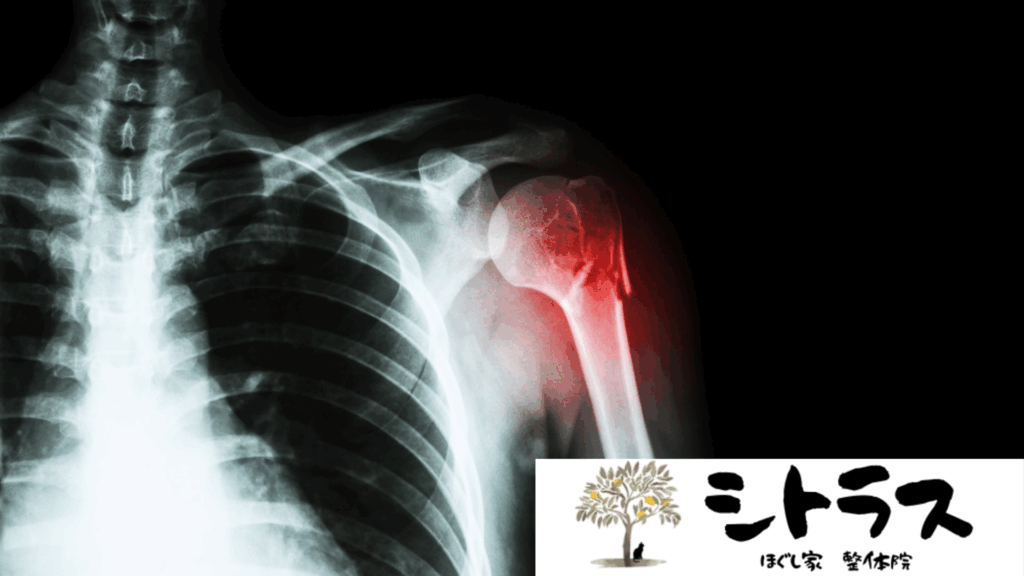

「上腕骨骨折(じょうわんこつこっせつ)」は、肩から肘にかけての骨である上腕骨が折れるケガです。転倒や交通事故、スポーツ外傷などで起こりやすく、高齢者では骨粗鬆症の影響で軽い転倒でも発生してしまうことがあります。

上腕骨骨折は折れる部位によって分類され、それぞれ特徴があります。

- 上腕骨近位端骨折

肩に近い部分の骨折。高齢者に多く、肩関節の動きが制限されやすい。 - 上腕骨骨幹部骨折

上腕の中央部分の骨折。交通事故やスポーツ外傷で発生。橈骨神経を損傷することがある。 - 上腕骨遠位端骨折

肘に近い骨折。小児では顆上骨折、成人では顆間骨折が代表的。肘関節の可動域制限に注意が必要。